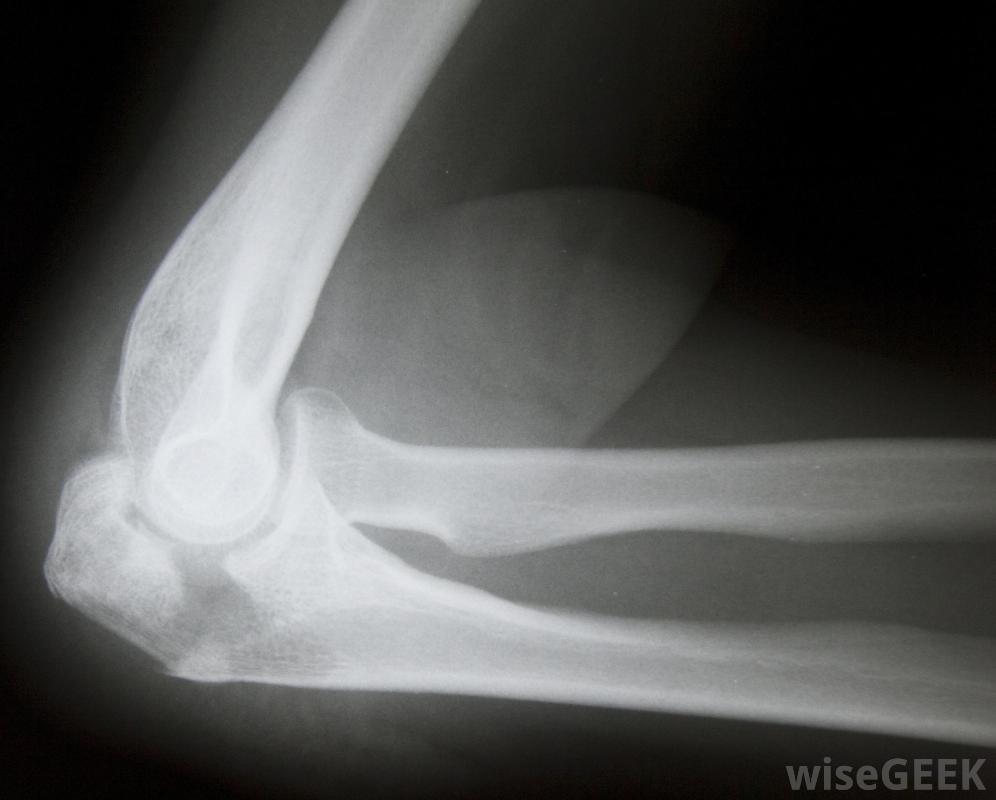

髁突是骨的圓形部分,通常位于關節內,并與另一塊骨頭相連。當這部分骨頭因撞擊或扭曲而破裂時,髁狀突骨折。這種情況可能發生在肘部、膝蓋或身體中存在髁狀突的其他關節處。治療髁狀突骨折通常從固定受影響的關節或骨骼開始,以防止進一步的損傷和減輕疼痛。最初的治療通常包括米飯過程,即休息、冰敷、壓迫,為了正確診斷髁狀突骨折,需要進行X光檢查受傷后應立即咨詢醫生,但在試圖移動患者之前,必須正確固定受影響區域。輕微的髁狀突骨折可以很容易地治療,但更復雜的骨折需要更密集的治療,因此,最好盡量防止髁突過度損傷。為了正確診斷髁突骨折并評估損傷的嚴重程度,可能需要進行x光檢查。如果沒有骨碎片,通常可以避免手術,但如果骨頭的任何部分已經分離,手術可能是必要的,以清除骨碎片和可能的其他受損組織如果骨的任何部分與髁狀突骨折分離,則可能需要進行手術。輕度至中度髁狀突骨折通常會使用消炎藥物和固定醫生可能會在愈合過程中使用硬石膏來防止骨頭移動。這種石膏可以保護骨骼不受進一步的傷害,防止移動,并增加刺激血液流動的壓力,加快愈合過程。還可以開止痛藥,由于髁狀突骨折可能是相當痛苦的情況,這取決于損傷的嚴重程度。髁狀突骨折的初始治療通常需要冰敷如果需要手術,愈合時間會延長,而且手術后留下的開放性傷口也需要治療。感染會使治療過程復雜化,所以傷口必須時刻保持清潔和干燥。傷口愈合前應定期更換敷料,像較小的骨折一樣,患處需要長時間固定。愈合時間可從幾周到幾個月不等一旦傷口充分愈合,患者可能需要進行身體康復,以恢復受影響區域的功能和活動能力。醫生可能會使用硬石膏來防止骨頭受損在治療過程中移動。